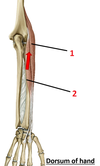

1? 2?

1: Teres major muscle

2: Latissimus dorsi muscle